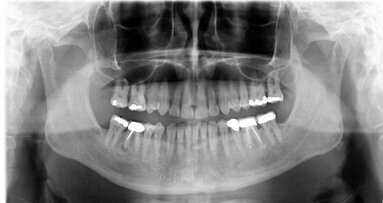

Pacjent zgłosił się do leczenia z powodu pogorszenia estetyki uśmiechu. Zauważył stopniowy ubytek długości zębów siecznych, co odbierał jako wizualne objawy starzenia oraz narastające objawy dysfunkcji narządu żucia w postaci epizodów zgrzytania, zaciskania oraz trzasków w stawie skroniowo-żuchwowym. W wywiadzie i badaniu nie stwierdzono przeciwwskazań do leczenia. Pierwszy etap leczenia pacjenta opisano w nr 1/2014 wyd. polskie Cosmetic. International magazine of aesthetic medicine & dentistry.

Stan przed leczeniem pokazano na rycinach 26 i 27, po leczeniu: na rycinach 28-31.